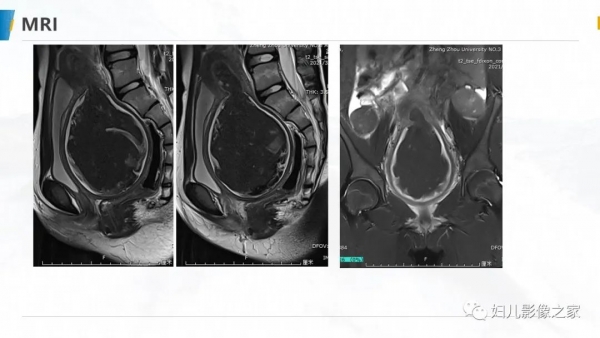

病例1

女,10岁,以“间断下腹痛7天”为主诉入院。入院查体:生命体征平稳, 心肺听诊无异常,腹软,肝脾未及,余无明显异常。

专科检查:外阴发育尚可,处女膜开口较小,棉签探入约4cm,无膨 隆,肛诊:子宫、宫颈膨隆,最低处距处女膜约4cm。

辅助检查:彩超(县中医院,2021-10-08):子宫体积增大,子 宫肌层变薄,内膜线消失,宫腔扩张,子宫颈管扩张,内充满大量液 性暗区,呈密集点状,阴道未见明显扩张。提示:1.胆囊内强回声2.胆 囊壁毛糙3.考虑处女膜闭锁。